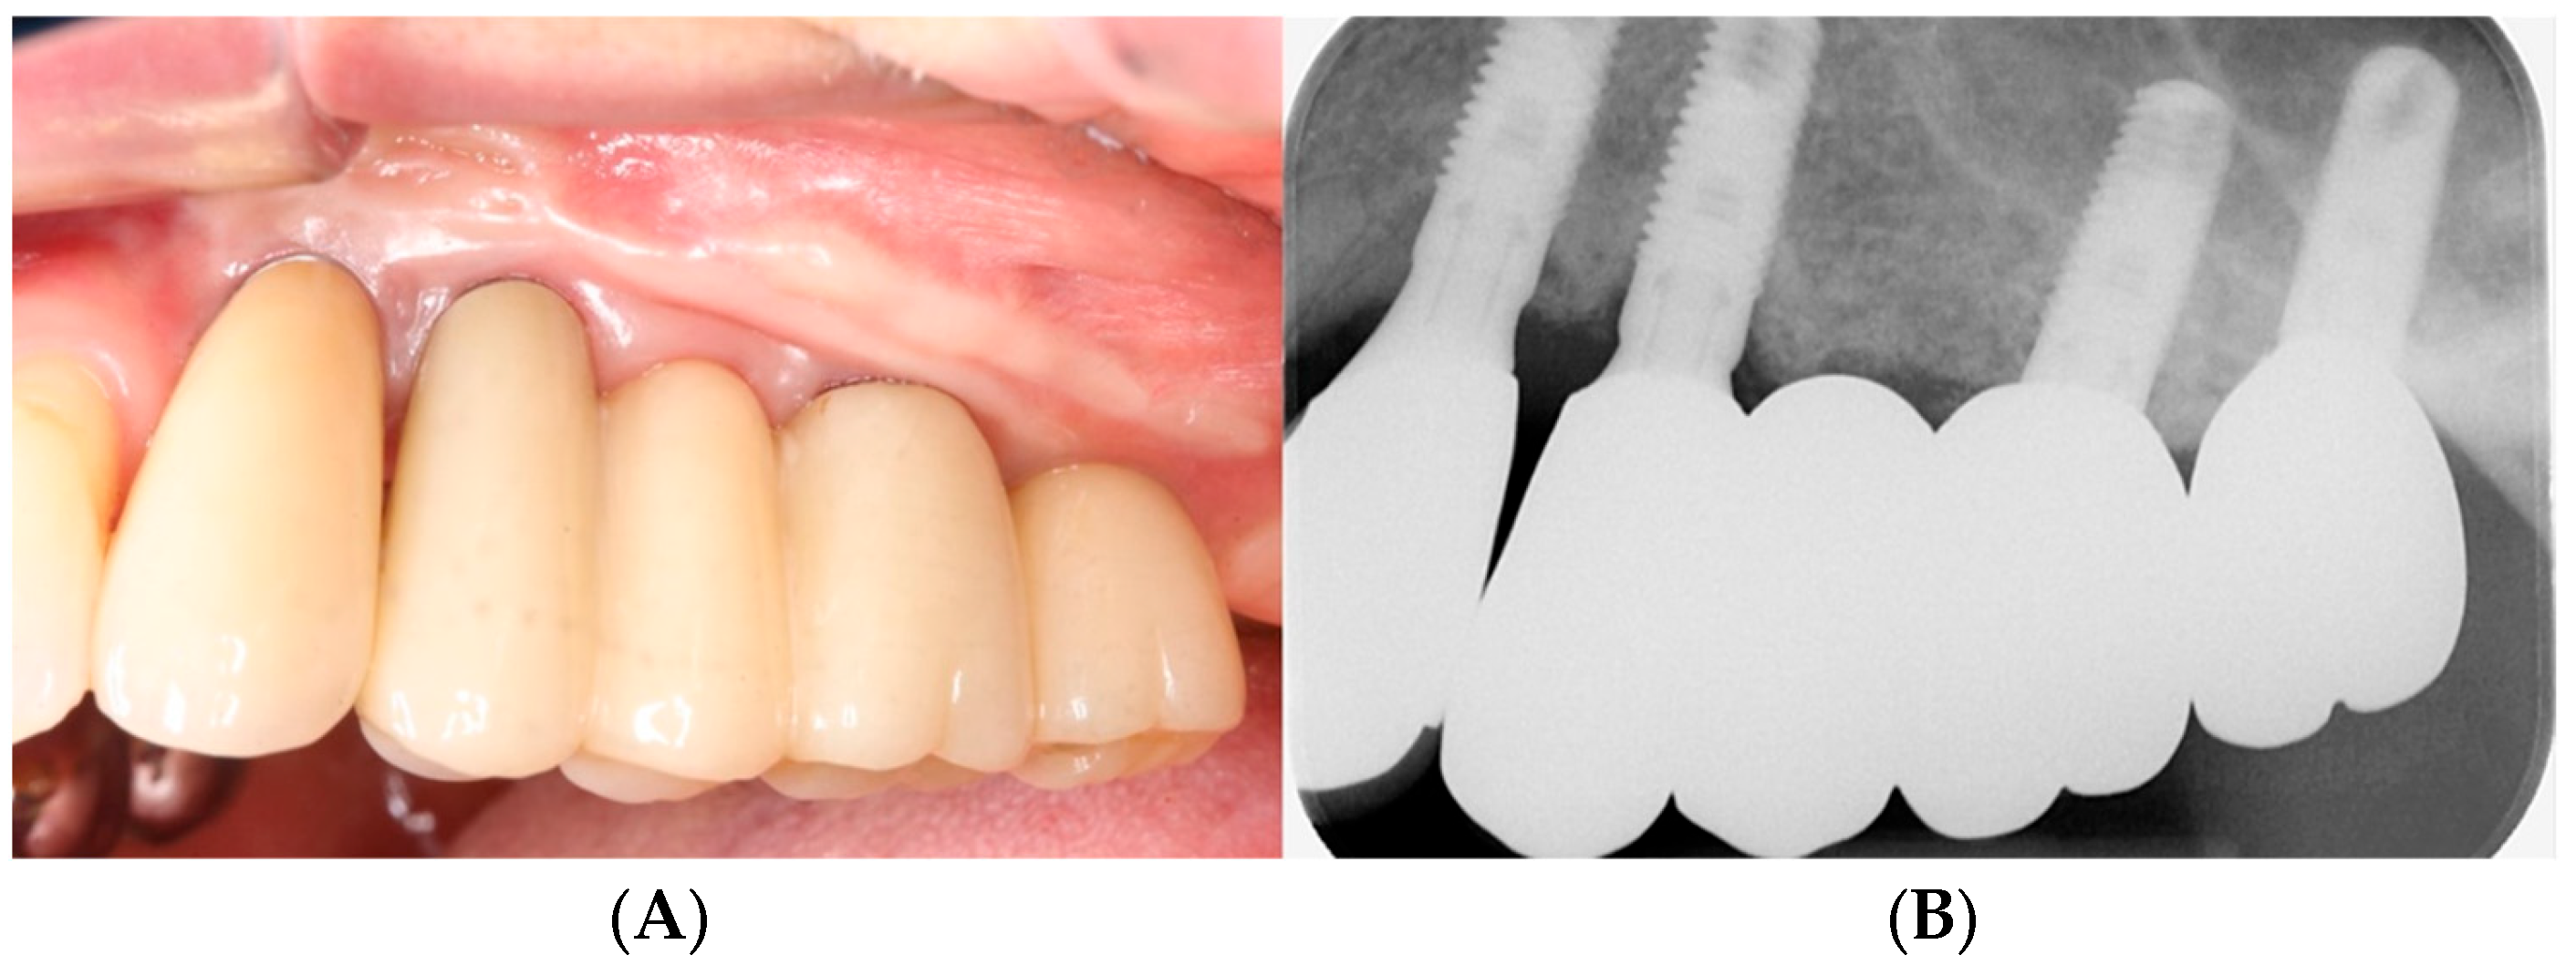

3.1. Clinical Results

3.2. Radiographic Results